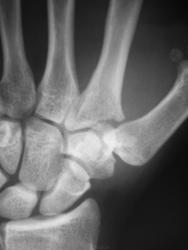

Пол пациента: Мужской пол Тип патологии: Травма Область исследования: Скелетно-мышечная система Методы исследования: Rg Травма. Пациент направлен на рентгенографию лучезапястного сустава. https://radiomed.ru/sites/default/files/styles/case_slider_image/public/user/12/2.pb240009.jpg?itok=Q_2dED98 https://radiomed.ru/sites/default/files/styles/case_slider_image/public/user/12/3.pb240009a.jpg?itok=_USHqTOg https://radiomed.ru/sites/default/files/styles/case_slider_image/public/user/12/4.pb240010a.jpg?itok=euelnlI2 ID:17025 Чт, 24/11/2011 - 19:49 #1 tatyana Не на сайте Был на сайте: 4 года 1 месяц назад Зарегистрирован: 24.06.2009 - 08:33 Публикации: 2090 перелом основания 2 пястной кости "самоуверенность дилетантов - предмет зависти профессионалов" Чт, 24/11/2011 - 21:18 #2 nnemo Не на сайте Был на сайте: 11 лет 1 месяц назад Зарегистрирован: 13.09.2011 - 18:32 Публикации: 561 tatyana wrote: перелом основания 2 пястной кости +1 Чт, 24/11/2011 - 22:14 #3 И.Бондаренко Не на сайте Был на сайте: 19 часов 41 минут назад Зарегистрирован: 13.09.2011 - 22:55 Публикации: 9206 Оскольчатый перелом основания 2 пястной кости, со смещением. Чт, 24/11/2011 - 22:26 #4 Bob Не на сайте Был на сайте: 11 лет 11 месяцев назад Зарегистрирован: 20.08.2011 - 20:06 Публикации: 218 +1 Пт, 25/11/2011 - 02:28 #5 Makcimalist Не на сайте Был на сайте: 11 лет 9 месяцев назад Зарегистрирован: 08.05.2010 - 14:28 Публикации: 1994 И.Бондаренко wrote: Оскольчатый перелом основания 2 пястной кости, со смещением. И я вскладчину! -------------- "Просто, по видимости, не видеть логики в очевидных вещах - это тоже одно из свойств некоторых умов, наряду с грустными думами о свойствах ума других." © Vega 08/10/2011

перелом основания 2 пястной кости

Оскольчатый перелом основания 2 пястной кости, со смещением.